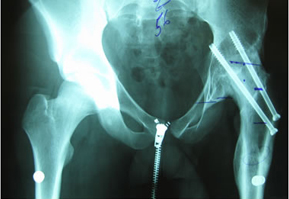

He was in his usual state of good health until age 14 when he became spontaneously septic. He was placed on ID pressors and subsequently lost his toes from vasoconstriction. He developed AVN of the femoral head. He does not think he was on any prednisone. He was then treated with a hip fusion. During the hip fusion the surgeon decided to do a subtrochanteric osteotomy which left the patient with a deformed proximal femur. He was placed in a hip spica cast for over 5 months. He believes he was also infected in the cast, but after speaking to him it sounds as if he had wound breakdown from the cast and not a deep infection.

| You will notice when you take out the pelvic obliquity it is 45 degrees |